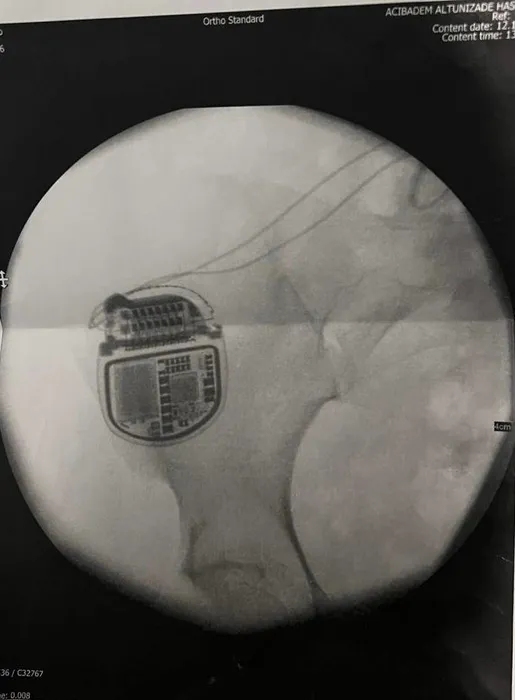

Z.T.’nin devam eden ağrıları sonucu omurgasına da pil takıldı. 6 yılda bir değiştirilmesi gereken pilin maliyeti ise 1,5 milyon TL. Estetik ameliyat sonrasında çok sayıda ilaca rağmen şiddetli ağrılar çeken Z.T., savcılığa giderek Cihantimur hakkında şikayetçi oldu.